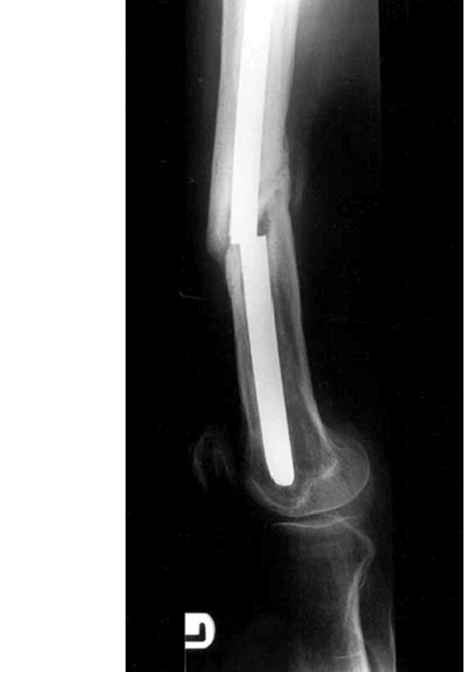

IM Nail Concepts Orthopedics Concepts IM Nail Concepts Figure 9.4: Titanium IM femoral nail. EXAMINER: What d…

IM Nail Biomechanics IM Nail Biomechanics E X A M I N E R: This is a radiograph of a broken femoral nail that…

This mock oral examination concept review focuses on the biomechanics of intramedullary (IM) nails in orthope…